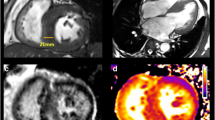

Left ventricular patterns in HCM, each drawing is accompanied by its corresponding image, (A, a) normal LV, (B, b) sigmoid septum showing SAM of mitral valve (white arrow), (C, c) reversed septal contour, note that there is no signs of LVOT, (D, d) mid ventricular hypertrophy, (E, e) Apical HCM, (F, f) symmetric HCM.

Stress perfusion CMR may be performed in same setting as a LGE CMR study [77, 78]. The severity of myocardial perfusion defects correlate with areas of maximal wall thickness and the presence of CMR defined fibrosis in patients with HCM [79]. These studies suggest that microvascular abnormalities precede and predispose to the development of myocardial fibrosis. When present, perfusion abnormalities may represent an early risk marker and a possible therapeutic target [80].